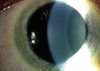

Uveitis is a general term for intraocular inflammation and includes a large number of clinical phenotypes. As a group of disorders, it is responsible for 10% of all registered blind patients under the age of 65 years. Immune-mediated uveitis may be associated with a systemic disease or may be localized to the eye. The pro-inflammatory cytokines interleukin (IL)-1beta, IL-2, IL-6, interferon-gamma and tumor necrosis factor-alpha have all been detected within the ocular fluids or tissues in the inflamed eye together with others, such as IL-4, IL-5, IL-10 and transforming growth factor-beta. The chemokines IL-8, monocyte chemoattractant protein-1, macrophage inflammatory protein (MIP)-1alpha, MIP-1beta and fractalkine are also thought to be involved in the associated inflammatory response. There have been a number of studies in recent years investigating cytokine profiles in different forms of uveitis with a view to determining what cytokines are important in the inflamed eye. This review attempts to present the current state of knowledge from in vitro and in vivo research on the inflammatory cytokines in intraocular inflammatory diseases.